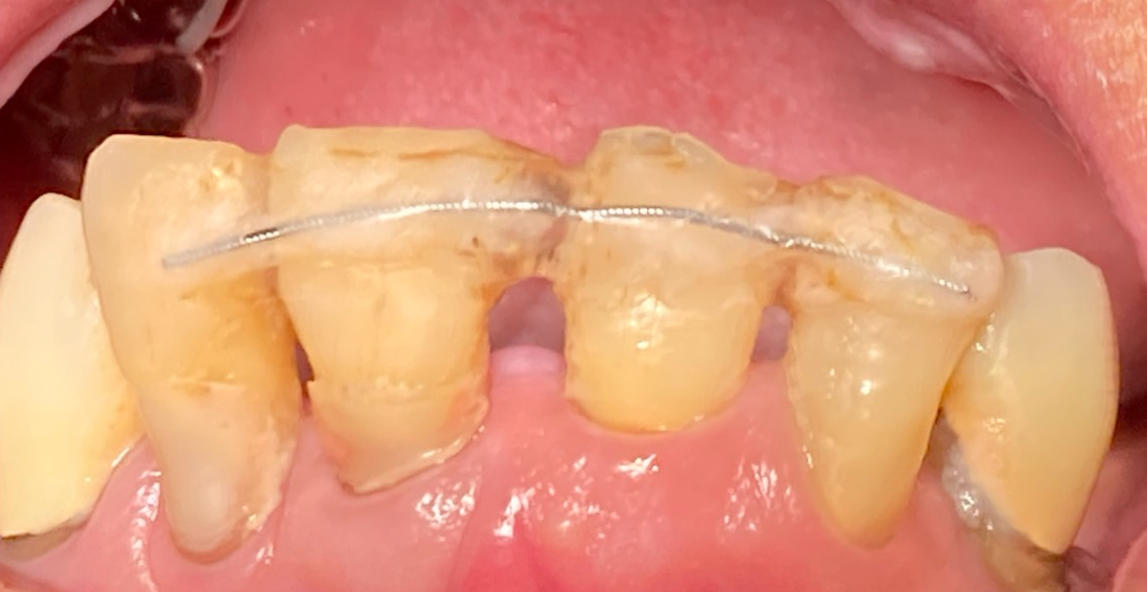

【治療開始時の状態】

●排膿: 前歯と奥歯の歯ぐきから、指で押すと膿が出る状態。

●動揺: 歯を支える骨が溶けているためグラつきがあり、ワイヤーで隣の歯と固定して維持している状態。

●骨の状態: X線検査にて、歯を支える歯槽骨の著しい吸収(骨が溶けて減っていること)を確認。

【診断】

重度歯周炎(広汎性重度慢性歯周炎の急性発作を含む)